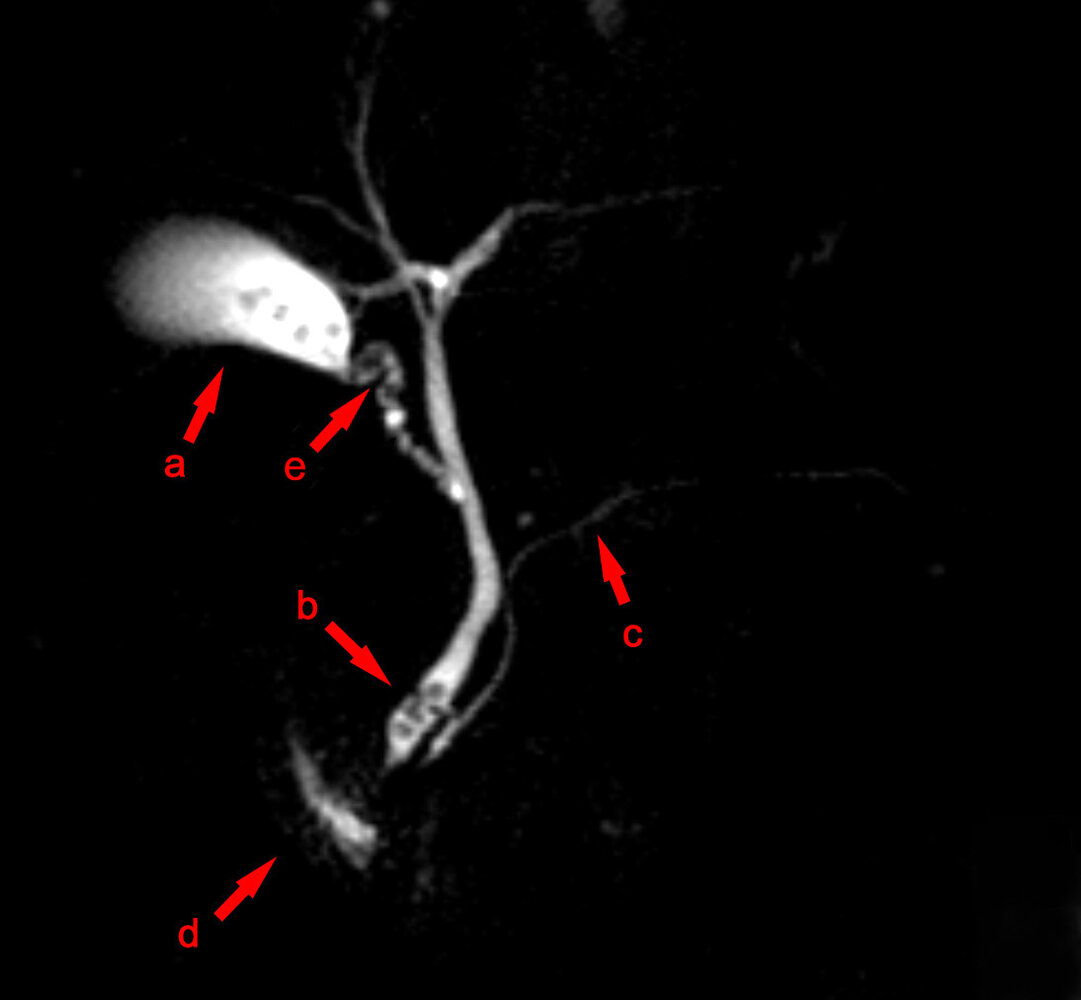

MRI abdomen without and with IV contrast with MRCP

• Indication: an alternative confirmatory imaging modality if ultrasound is inconclusive [8][11][12][16]

• Supportive findings: similar to CT findings